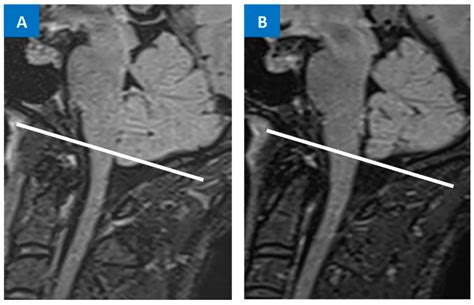

Receiving a radiology report that mentions cerebral tonsils low lying can be a source of significant anxiety. You may be wondering what these terms mean, whether they indicate a serious condition, or if you should be concerned about your neurological health. In medical imaging, particularly MRI scans, the cerebellar tonsils are structures located at the base of the brain, specifically at the lower part of the cerebellum. When these structures extend below the opening at the base of the skull—known as the foramen magnum—they are described as low-lying. Understanding this anatomical variation is the first step toward determining whether it is a harmless incidental finding or a sign of a condition requiring medical intervention, such as Chiari malformation.

The cerebellum is responsible for coordinating voluntary movements, balance, and posture. The cerebral tonsils low lying (more accurately referred to as cerebellar tonsils) are the two rounded projections at the very bottom of the cerebellum. In a typical anatomical arrangement, these tonsils sit safely above the foramen magnum, which is the large opening in the occipital bone of the skull where the spinal cord passes through to meet the brainstem.

When these tonsils descend into the foramen magnum, the condition is often scrutinized by neurologists and neurosurgeons. The severity is generally measured by the number of millimeters that the tonsils extend below the line of the foramen magnum. While the medical community has debated what constitutes a "pathological" descent, a displacement of 5 millimeters or more is commonly used as a clinical threshold for a diagnosis of Chiari I malformation, though clinical symptoms are often a more important factor than the measurement alone.